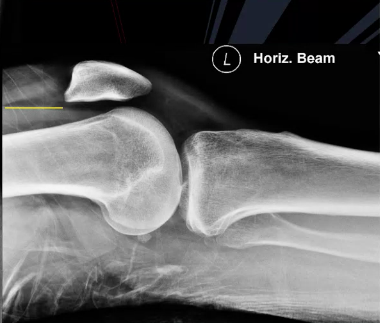

A 30 year old man presented to the ED with left knee pain after a cycling accident.

On examination there was no deformity, but it was painful for him to weight-bear. Movements of his knee were painful, and this limited his movements.

What is a lipohemarthrosis?

Results from an intra-articular fracture with escape of fat and blood from the bone marrow into the joint, and is most frequently seen in the knee.

What normal variant can be seen in this image?